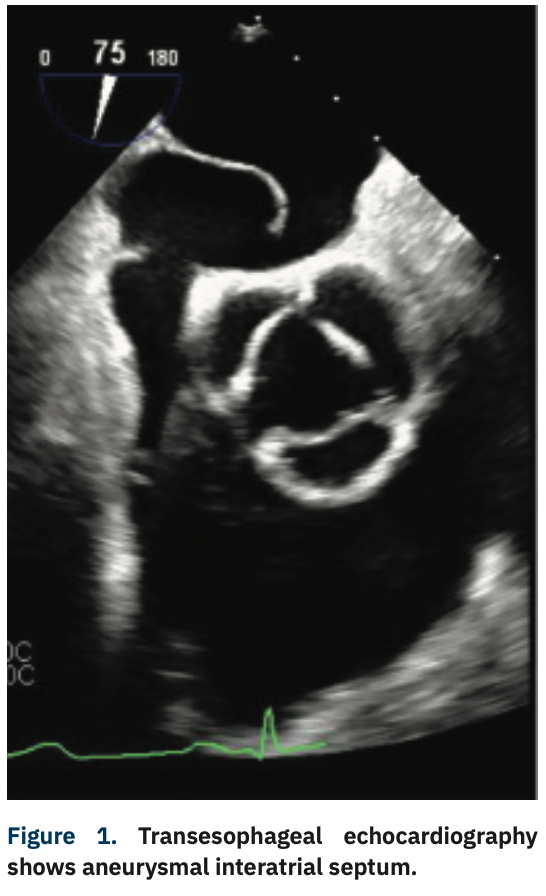

He was admitted with diagnosis of acute hypoxic respiratory failure secondary to a presumptive diagnosis of hypersensitivity pneumonitis given his history and was started on intravenous steroids. Despite treatment, he continued to get progressively hypoxemic, requiring high-flow O2. After an extensive and detailed pulmonary workup at the outside facility, he was transferred to our facility for further evaluation and management. Repeat echocardiography demonstrated a large PFO using agitated saline. A subsequent transesophageal echocardiogram (TEE) revealed normal biventricular size and function, an atrial septal aneurysm (Figure 1), and color-flow Doppler suggested the presence of a PFO with predominant right-to-left shunting (Figure 2). Right heart catheterization demonstrated normal central filling pressures with no evidence of left-to-right shunting.